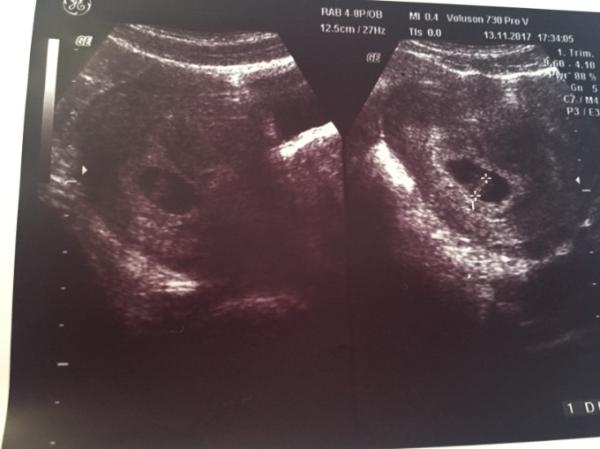

Hallo Leute, gestern hatte ich den lang ersehnten Frauenarzt Termin (7+1)

Das Baby ist zeitgerecht entwickelt und das Herzchen schlägt.

Ach wie schön Das freut mich ganz arg für Dich. Und so ein schönes Bild hast du auch noch bekommen. Jetzt kannst Du Dich ersteinmal entspannen.

Das sieht wunderbar aus. Hoffe, dass ich auch so ein schönes Bild nächste Woche bekomme.